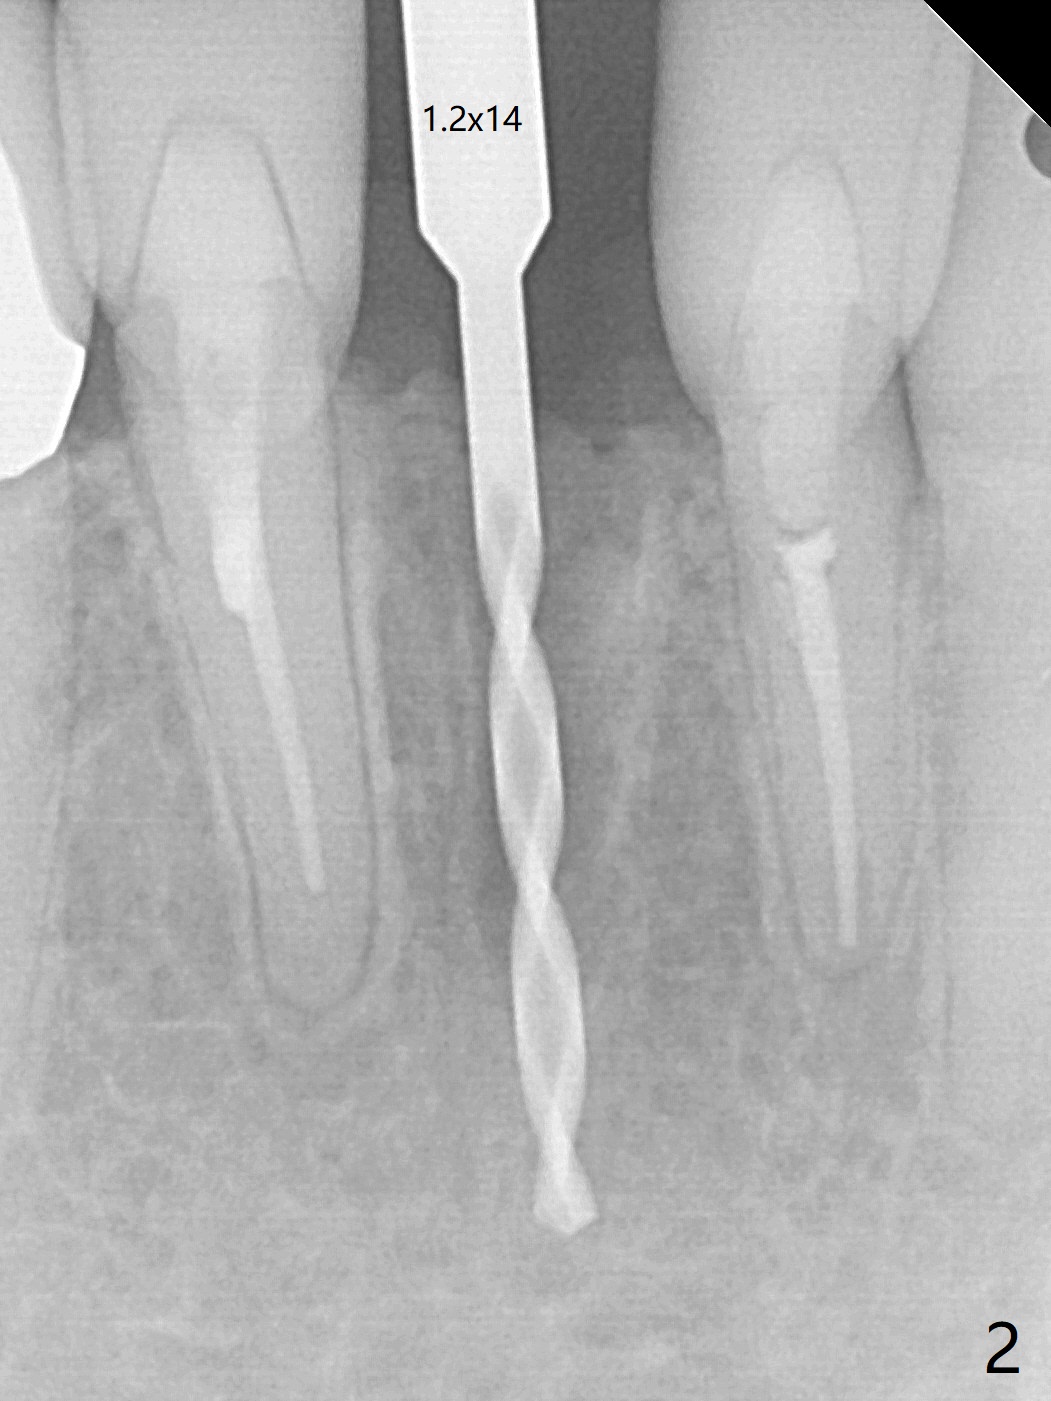

A drawback of implant planning at #25 is not to use a preop PA (Fig.1 (^ fracture line)). The initial trajectory seems to be alright (Fig.2), but a 2.5x14(2) mm implant placed is close to the tooth #26 (Fig.3). In fact the affected tooth is deviated distal; osteotomy should be initiated in the mesial slope of the socket (Fig.4 red line). The final trajectory appears to be perfect (Fig.5). Furthermore the 1st intraop PA should be analyzed carefully (Fig.6). A new osteotomy should be established mesial or the existing one should be moved mesial with Lindamann bur (Fig.7). The distal implant placement may be related to more bone loss in the distal crest 3.5 months postop (Fig.8) and more severe distal papillary recession (Fig.9 *). The bone density increases at the levels of the non-thread and thread portions of the implant (in the original socket) nearly 10 months post cementation (Fig.11 *, <). There is no bone loss 16 months post cementation (Fig.12).